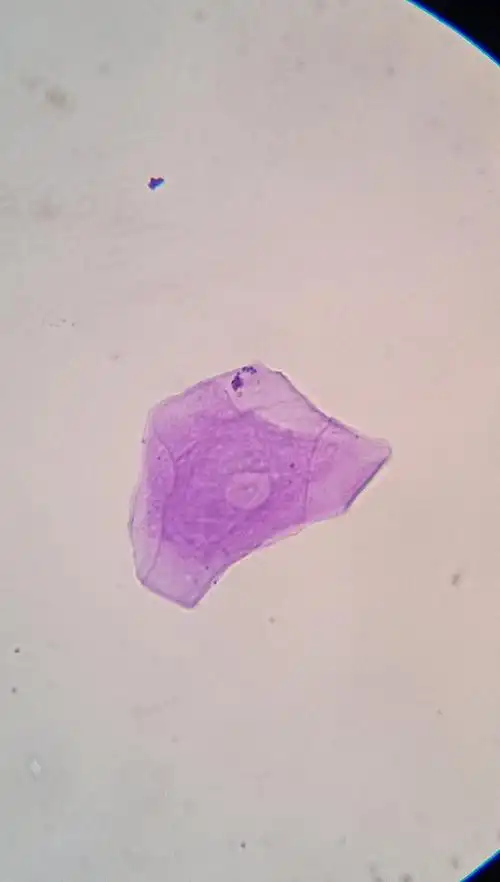

显微镜下的人体口腔上皮细胞,叶横切临时装片,鸡蛋结构

人的口腔上皮细胞(染色)